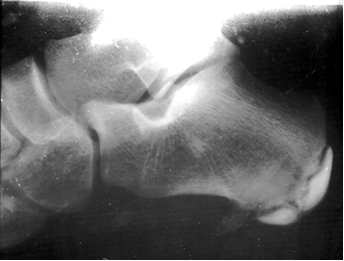

Zdjęcie radiologiczne przedstawia radiogram stopy 12-letniego chłopca, skarżącego się od 3 tygodni na ból piety, trudności w chodzeniu i niewielki obrzęk okolicy guza piętowego. Obraz taki jest charakterystyczny dla :